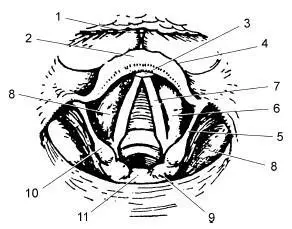

Ларингоскопическая картина гортани при непрямой ларингоскопии весьма характерна (рис. 19.2), и поскольку она является результатом зеркального отображения истинной картины и зеркало располагается под углом в 45° к горизонтальной плоскости (принцип перископа), отображаемое располагается в вертикальной плоскости. При таком расположении отображаемой эндоскопической картины в верхней части зеркала видны передние отделы гортани, нередко прикрытые у комиссуры надгортанником; задние отделы, в том числе черпала и межчерпаловидное пространство, отображаются в нижней части зеркала (рис. 19.3).

Рис. 19.2.Внутренний вид гортани при непрямой ларингоскопии:

1 – языкоглоточная складка; 2 – надгортанник; 3 – бугорок надгортанника; 4 – свободный край надгортанника; 5 – черпалонадгортанная складка; 6 – складки преддверия; 7 – голосовые складки; 8 – желудочек гортани; 9 – черпаловидный хрящ с рожковидным хрящем; 10 – клиновидный хрящ; 11 – межчерпаловидное пространство

Поскольку при непрямой ларингоскопии осмотр гортани возможен только одним левым глазом, т. е. монокулярно (в чем легко убедиться при его закрытии), то все элементы гортани видны в одной плоскости, хотя голосовые складки располагаются на 3–4 см ниже края надгортанника. Боковые стенки гортани визуализируются резко укороченными и как бы в профиль. Сверху, т. е. фактически спереди, видна часть корня языка с язычной миндалиной (см. рис. 19.2, 1), затем бледно-розовый надгортанник ( 2), свободный край которого при фонации звука «и» поднимается, освобождая для обозрения полость гортани. Непосредственно под надгортанником в центре его края иногда можно увидеть небольшой бугорок (3) – tuberculum epiglotticum, образованный ножкой надгортанника. Ниже и кзади надгортанника, расходясь от угла щитовидного хряща и комиссуры к черпаловидным хрящам, расположены голосовые складки (7) белесовато-перламутрового цвета, легко идентифицирующиеся по характерным трепетным движениям, чутко реагирующие даже на незначительную попытку фонации. Во время спокойного дыхания просвет гортани имеет вид равнобедренного треугольника, боковые стороны которого представлены голосовыми складками, вершина как бы упирается в надгортанник и часто им прикрыта. Надгортанник является препятствием для осмотра передней стенки гортани. Для преодоления этого препятствия применяют позицию Тюрка, в которой осматриваемый запрокидывает голову, а врач проводит непрямую ларингоскопию стоя, как бы сверху вниз (рис. 19.4, б). Для лучшего обзора задних отделов гортани применяют позицию Киллиана, при которой врач осматривает гортань снизу (стоя на одном колене перед больным), а больной наклоняет голову книзу (а).

В верхнелатеральных областях полости гортани над голосовыми складками видны складки преддверия, розовые и более массивные (см. рис. 19.2, 6). Они отделены от голосовых складок пространствами, лучше просматривающимися у худых лиц. Эти пространства представляют собой входы в желудочки гортани. Межчерпаловидное пространство ( 11), являющееся как бы основанием треугольной щели гортани, ограничено черпаловидными хрящами, которые видны в виде двух булавовидных утолщений (9), покрытых розовой слизистой оболочкой. При фонации видно, как они вращаются навстречу друг другу своими передними частями и сближают прикрепленные к ним голосовые складки. Слизистая оболочка, покрывающая заднюю стенку гортани, при расхождении черпаловидных хрящей на вдохе становится гладкой; при фонации, когда черпаловидные хрящи сближаются, она собирается в мелкие складки. У некоторых лиц черпаловидные хрящи соприкасаются настолько тесно, что как бы заходят друг за друга. От черпаловидных хрящей направляются вверх и вперед черпалонадгортанные складки, которые достигают латеральных краев надгортанника и вместе с ним служат верхней границей входа в гортань. Иногда, при субатрофичной слизистой оболочке, в толще черпалонадгортанных складок можно видеть небольшие возвышения над черпаловидными хрящами; это – рожковидные (санториниевы [6] Описаны итальянским врачом, физиологом и анатомом S. Santorio (1561–1636).

При непрямой ларингоскопии видны и некоторые другие анатомические образования. Так, над надгортанником, фактически впереди него, видны ямки надгортанника, образованные латеральной язычно-надгортанной складкой и разделенные медиальной языко-глоточной складкой (см. рис. 19.2, 1). Боковые части надгортанника соединяются со стенками глотки при помощи глоточно-надгортанных складок, которые прикрывают вход в грушевидные синусы гипофаринкса. Во время расширения голосовой щели возникает уменьшение объема этих синусов, во время сужения голосовой щели их объем увеличивается. Указанный феномен возникает за счет сокращения межчерпаловидных и черпало-надгортанных мышц. Ему придают большое диагностическое значение, поскольку его отсутствие, особенно на одной стороне, является наиболее ранним признаком опухолевой инфильтрации указанных мышц или начинающегося их нейрогенного поражения.